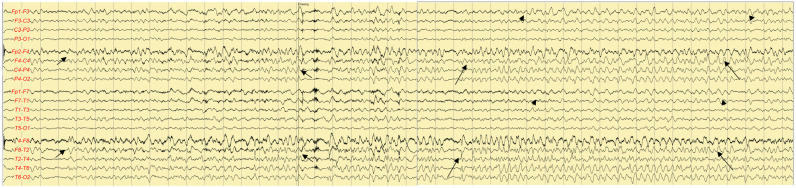

Herpes simplex encephalitis (HSE) is a common viral encephalitis that can be fatal if not adequately treated. Fever, cerebrospinal fluid (CSF) pleocytosis, and typical neuroimaging findings are commonly observed in HSE cases. We encountered a patient with HSE who did not exhibit these classic clinical features. A 63-year-old male presented with his first-ever seizure. Fever did not develop until the fourth day of admission, and neither neuroimaging nor CSF analysis revealed abnormalities. Under suspicion of autoimmune encephalitis, methylprednisolone was administered. Subsequently, when the patient developed fever, a follow-up neuroimaging study was performed and revealed abnormalities consistent with HSE. The patient was promptly treated with acyclovir, which led to a full recovery. Diagnosing HSE in patients who present without fever or CSF pleocytosis and with typical neuroimaging findings poses a challenge. Therefore, prior to initiating immunosuppressive treatment, it is crucial to closely observe patients and to conduct follow-up tests, including neuroimaging and CSF analysis.